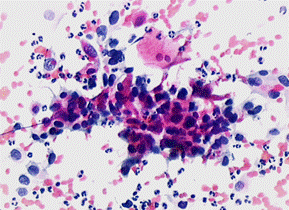

7.腺细胞异常:比较少见,包括非典型腺细胞(AGC)、原位腺癌(AIS)和腺癌(AC),这三种报告结果均属于异常报告结果,如果有腺上皮细胞的异常,临床医生结合临床其它资料分析,必要时应尽快行阴道镜检查、子宫颈活检及子宫颈管搔刮术等以明确诊断。